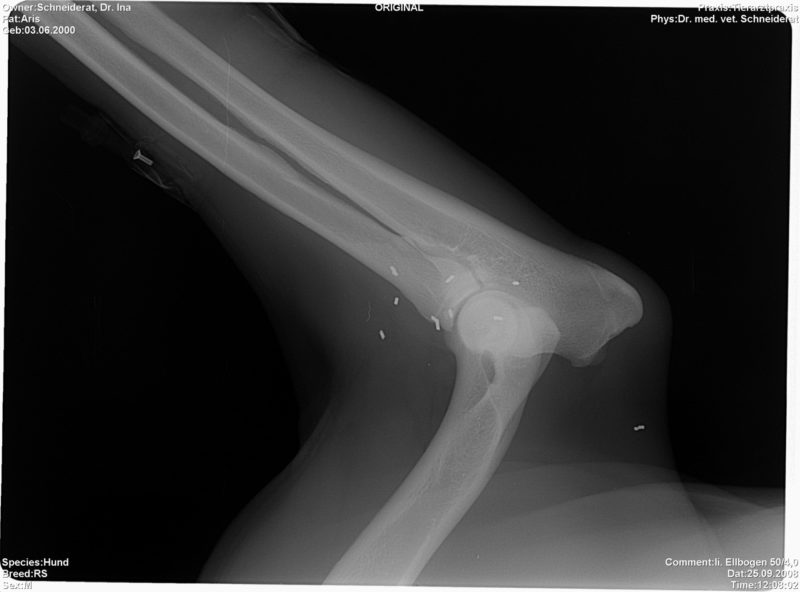

Bei einer eingehenden Lahmheitsuntersuchung fällt besonders der aufgezogene Rücken, sowohl im Stand als auch in der Bewegung, auf. Das für Hüft- und Beckenprobleme charakteristische „Po-Wackeln“ zeigte Tommy schon immer, allerdings hielten seine Besitzer das bisher nicht für ein Krankheitssymptom. Schließlich humpelte er ja bisher nicht. Neben weiteren Auffälligkeiten des Gangbildes ist vor allem der Schwung aus der Hinterhand und die Beweglichkeit der Wirbelsäule deutlich reduziert. Tommy legt sich beim Laufen regelrecht auf die Vorderhand. Beim Abtasten zeigt Tommy Schmerzen im Rücken sowie im Becken- und Hüftbereich. Auch die Triggerpunkte der Ellbogen reagieren auf beiden Seiten schon auf leichten Druck. Der Verdacht auf Arthrose in den Hüft-, Wirbel- und Ellbogengelenken wird  durch anschließende Röntgenbilder bestätigt. Was nun? Arthrose ist nicht heilbar. Also müsste Tommys Frauchen damit rechnen, ihn für den Rest seines Lebens immer wieder wegen Schmerzen behandeln zu lassen.

Bei der Goldimplantation werden dem Patienten nach einer sehr ausführlichen Untersuchung in Sedierung 1-3 Millimeter lange Golddrahtstückchen mittels einer Hohlnadel an Akupunkturpunkte und/oder spezielle lokale Punkte injiziert. Hauptanliegen der Goldimplantation ist die ganzheitliche Therapie des Körpers. Es wird also nicht z.B. eine einzelne Gelenkerkrankung behandelt, sondern die Bewegung als Einheit harmonisiert. Durch die entzündungslindernde Wirkung der Goldimplantate werden durch Entzündungen verursachte Schmerzen gelindert, die Durchblutung in diesem Gebiet verbessert und somit der Stoffwechsel und das Gangbild harmonisiert. Übrigens sind die Goldimplantate kein Hindernis für andere Behandlungsmethoden wie z.B. Akupunktur oder Chirurgie. Sie können sogar im Gegenteil oft sehr gut kombiniert werden. Bei punktgenauer Implantation durch spezialisierte Tierärzte stellt sich in der Regel recht bald eine Schmerzfreiheit oder zumindest –armut ein. Der Patient kann sich wieder besser bewegen und erlangt somit mehr Lebensqualität und Lebensfreude. Vorhandene Arthrosen werden nicht beseitigt, doch durch die Schmerztherapie können Schmerzmedikamente erheblich reduziert oder sogar abgesetzt werden. Da das Gold im Körper nicht abgebaut wird, hält diese Wirkung dauerhaft an.

Tommy bekommt in Narkose Goldimplantate an die zu seiner Problematik (Hüfte, Wirbelsäule und Ellbogen) passenden Akupunkturpunkte und zusätzlich ausgesuchte lokale Punkte. Er bewegt sich bereits wenige Tage nach der Goldimplantation (GI) deutlich lockerer. Schon nach wenigen Wochen sind die Triggerpunkte beim Abtasten nicht mehr sensibilisiert und Tommy spielt wieder fröhlich mit seinen Hundefreunden im Park. Diese Wirkung hält seit inzwischen sieben Jahren dauerhaft an, und Tommy hat viel Freude an seinem speziellen Senioren-Trainingsprogramm.